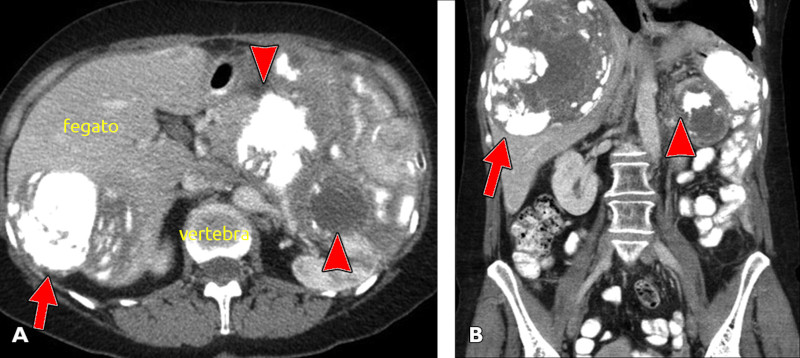

Liposarcoma

- Descrizione: Tumori maligni costituiti dalla proliferazione di tessuto cellulare adiposo.